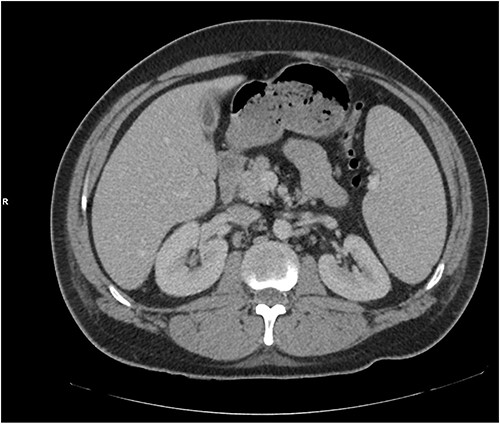

The patient was treated with IV piperacillin-tazobactam. However, he continued to have febrile temperature spikes. No growth was initially detected on blood cultures. The patient developed shortness of breath and respiratory alkalosis, for which a CT pulmonary angiography was done to exclude pulmonary embolism. Only dependent bilateral changes in the lower lobes and signs of mild pulmonary venous congestion were reported (Fig. 3). He was started on hydrocortisone, ethambutol, pyridoxine and rifampicin as empirical treatment for BCGosis. Hydrocortisone was eventually tailored down to prednisolone. Virology tests including hepatitis and immunodeficiency virus were run and these were negative. He continued spiking high temperatures and a repeat CT abdomen with IV contrast was performed which was largely unchanged from the previous scan (Fig. 4). An echocardiogram ruled out infective endocarditis. Incidentally he was in contact with a COVID-19 positive patient and was placed under quarantine for 14 days. Fortunately, he never developed COVID-19 infection. Another CT pulmonary angiography was performed in view of persisting shortness of breath but only mosaic attenuation in the lungs was present.

A CT pulmonary angiography was done to exclude pulmonary embolism. Only dependent bilateral changes in the lower lobes and signs of mild pulmonary venous congestion were noted.

A repeat CT abdomen with IV contrast was performed which was largely unchanged from the previous scan, save for mild pericholecystic fluid.